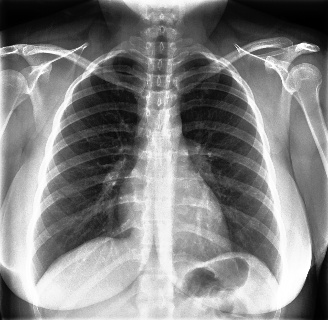

Qualitatively, Fig. 5 shows a significant improvement of the visual realism across all methods when using a drift of . The background is consistently black as in real brain MR images; the shape of the brain becomes more realistic, and the white and gray matter structure improves. For an analytical evaluation, we calculated the FID between our test data and 200 synthetically generated images from each method (100 CN, 100 AD). The results in Tab. 1 demonstrate that LD improves the ability of the model to generate realistic MRI slices for both healthy brains and brains with Alzheimer’s disease. For this reason, all following experiments were done with LD.

We use the Pix2Pix Zero model with a basic fine-tuned Stable Diffusion model to generate healthy brain MRIs from ones diagnosed with Alzheimer’s Disease and vice versa. We generate the counterfactual images by negating the ground truth label of the 200 test samples and conditioning the model on the negated label value and the source image. We compute image quality metrics, as well as the AUC, using a disease classification model trained on 600 real brain MRI slices (300 AD, 300 CN). Additionally, we determine the Structure Similarity Inced (SSIM) between the target and the source image to determine how well the identity of the source image is retained. The qualitative results in Fig. 6 , illustrate four examples from our two editing directions: from AD to CN and from CN to AD, respectively. When transitioning from AD to CN, the model primarily reduces the size of the ventricles. Conversely, in the CN to AD transformation, the ventricle size increases, accompanied by a worsening of brain atrophy.